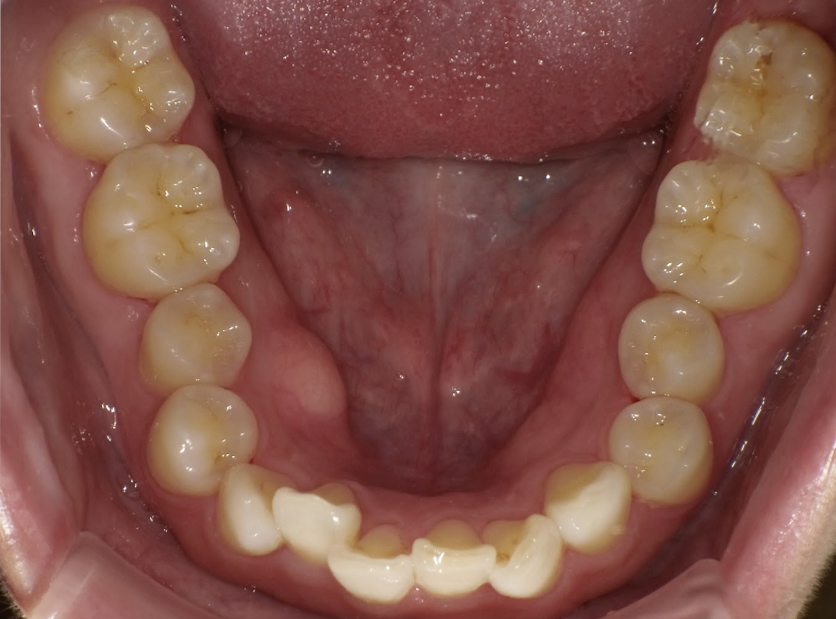

過蓋咬合

ガタガタを主訴に当院を受診され、上下前歯部に叢生(ガタガタ)と過蓋咬合(上の歯が下の歯を深く覆いかぶさっている状態)を認めました。

IPRを使用してマウスピース型矯正装置(インビザライン)を使用し過蓋咬合及び叢生の改善を行いました。

年齢/性別30代女性

抜歯部位非抜歯

治療期間1年6ヶ月